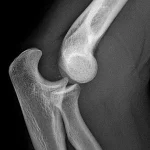

برای شروع درمان سریع، تشخیص درست بسیار مهم است. استفاده از رادیوگرافی، سیتیاسکن یا MRI برای ارزیابی نوع و محل شکستگی انجام میشود.

برای شکستگیهای شدیدتر یا جابجا شده، جراحی باز (ORIF) با استفاده از پیچ و پلاک انجام میشود.